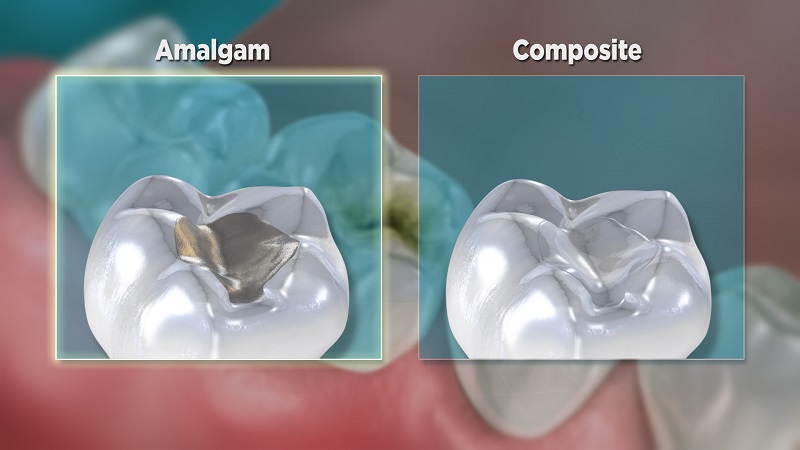

تفاوت آمالگام و کامپوزیت

تفاوت آمالگام و کامپوزیت: کدام یک بهتر است؟

پر کردن دندان با آمالگام یا کامپوزیت، مزایا و معایبی دارد. در ادامه درباره هر دو مورد توضیح میدهیم تا به شما هنگام انتخاب یکی از این دو روش کمک کنیم.

«دندانتان یک حفره دارد.» معمولا شنیدن این جمله از یک دندانپزشک ناخوشایند است. اما با وجود پیشرفتهای اخیر در دندانپزشکی، چندین شیوه مختلف برای ترمیم دندان وجود دارد. این در حالی است که در گذشته پرکنندههای آمالگام نقره سنتی تنها گزینه موجود بودند، امروزه در اکثر مطبهای دندانپزشکی از کامپوزیت نیز استفاده میشود.

مواد پرکننده آمالگام از انواع فلزات مانند: نقره، جیوه، روی و مس ساخته میشوند. بیشتر اوقات با نام فیلینگ نقره یا فلز شناخته میشود. این نوع پر کردن نسبت به کامپوزیت، بسیار مقرون به صرفهتر و دارای ماندگاری بیشتری است. در صورت مراقبت مناسب، فیلینگ آمالگام تا ۱۵ سال ماندگار است. از آنجا که از آلیاژ فلز استفاده میشود، پر کنندههای آمالگام در برابر آسیب دیدگی مقاومت بیشتری دارند. بنابراین برای ترمیم نواحی گسترده پوسیدگی انتخاب بهتری است.

با این وجود، در سالهای گذشته، به دلیل وجود جیوه در مواد پرکننده آمالگام، استفاده از این مواد کاهش یافته است. جیوه فلزی سنگین است و بعضی از افراد به آن حساسیت خاص یا آلرژی دارند. عیب دیگر مواد پرکننده آمالگام ظاهر آن است. هنگام خندیدن یا لبخند زدن، دندانهای پر شده با نقره بیشتر جلب توجه میکنند. به مرور زمان، پرکنندههای آمالگام باعث تیرگی ظاهر کل دندانها میشوند و آنها را مایل به خاکستری نشان میدهند که بر روی لبخند تاثیر منفی دارد.

پرکنندههای کامپوزیتی که به پرکنندههای رنگی دندان نیز معروفند، ساخته شده از اکریلیک و سرامیک هستند که قادرند به خوبی و زیبایی با مینای دندان طبیعی شما سازگار شوند. کامپوزیت ترمیم مطلوبتری را ارائه میدهد. همچنین در این نوع ترمیم، مینای دندان کمتر تراش میخورد و دندان به آماده سازی کمتری نیاز دارد. در نتیجه این امکان را فراهم میکند که ساختار طبیعی دندان خود را حفظ کنید.

معایب اصلی کامپوزیت، هزینه زیاد و طول عمر کم است. کامپوزیت دندان به عنوان روش درمانی جدیدی در دندانپزشکی، مانند آمالگام مقرون به صرفه نیست. کامپوزیت نسبت به آمالگام به جلسات درمان بیشتری نیاز دارد که باعث افزایش هزینه میشود. از طرفی کامپوزیت مانند آلیاژ فلز دوام ندارد و معمولا ماندگاری آن حدود ۷ تا ۱۰ سال به طول میکشد.

دندانهای جلویی هنگام لبخند زدن یا خندیدن به آسانی قابل مشاهدهاند پس با استفاده از کامپوزیت طبیعیتر به نظر میرسند. اما برای دندانهای عقبی که دیده نمیشوند و پوسیدگی بیشتری دارند، آمالگام به دلیل دوام و ماندگاری بیشتر انتخاب بهتری است. اگر درباره زیبایی و یا جیوه موجود در مواد نگران هستید، با دندانپزشک خود مشورت کنید آیا امکان جایگزینی مواد با تاج دندان، اینله و اینلی مناسب وجود دارد.